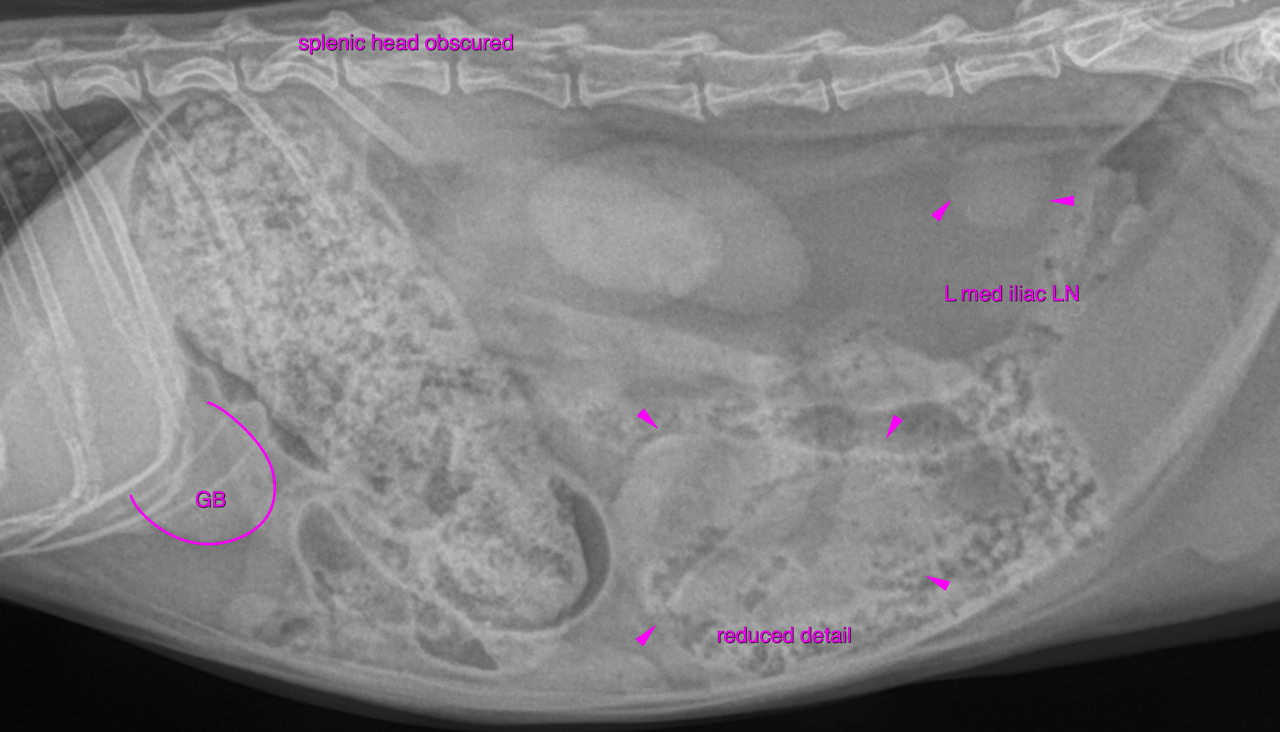

mediastinal fat. There is moderate generalized splenomegaly with rounded margins. The splenic head

is obscured on the lateral view, which is likely owing to the mass effect.

A round soft tissue opaque structure is seen between the liver and the moderately

distended and ingesta filled stomach, which is likely to be compatible with the

distended gallbladder. Theoretically this could represent a cranial abdominal

lymphadenomegaly or cyst as well. The left medial iliac lymph node reveals moderate enlargement and rounding.

The findings are suggestive for a multifocal neoplastic infiltrate involving the spleen

and lymph nodes. The bronchitis may be infectious (bacterial, viral, parasitic) or allergic in origin.